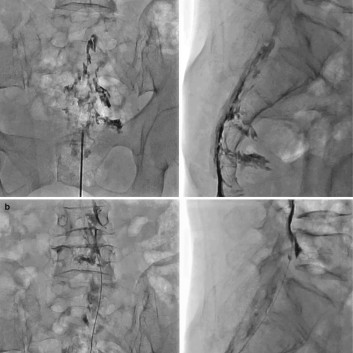

척추 통증의 원인이 되는 돌출 된 디스크나 좁아진 협착이 있는 경우 통증의 원인은 신경 주위의 유착과 부종 및 염증입니다. 경막외 신경성형술은 꼬리뼈에 있는 척추관으로 통하는 구멍으로 직경 1mm 미만의 카테터를 삽입하여 디스크와 협착증이 있는 부위까지 접근시켜 물리적으로 유착을 박리하고 화학적으로 염증과 부종을 줄여줍니다.

경막외 신경성형술은 인대강화주사와 심부신경주사로 접근이 어려운 척추의 중심관 병변 및 심한 유착성 병변 그리고 디스크 파열이 심각하여 주사제의 투여가 어려울 정도로 척추관의 압력이 높아져 있는 경우 의미 있게 치료에 적용 할 수 있으며 반복적인 인대강화주사 및 심부신경주사 치료 역시 신경성형술 만큼이나 효과적으로 디스크 치료에 적용할 수 있습니다. 다만 주사치료로 접근에 한계가 있을 때는 시술에 대한 고려가 필요 합니다.